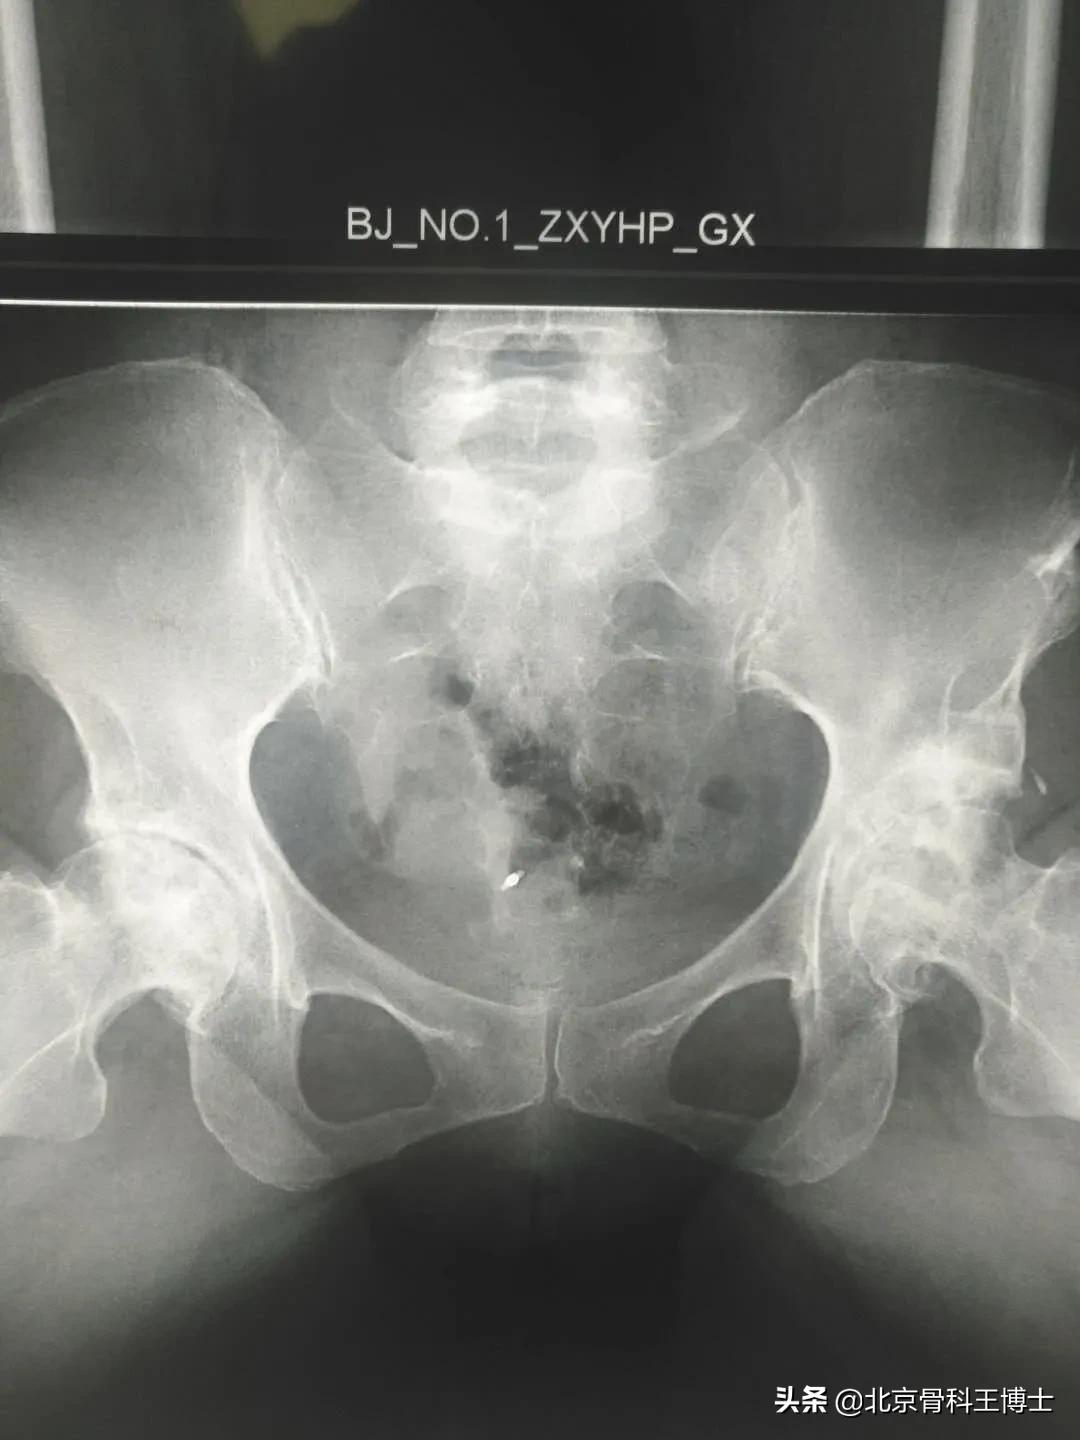

我研发的细胞移植治疗股骨头坏死保髋治疗,已经完成3500余例病人。有很多病人手术后已经超过10年。他们至今依然在各个行业从事着工作。有的病人甚至还从事着重体力劳动。大量的临床实践证明,股骨头坏死是完全能够治愈的。

细胞移植治疗股骨头坏死这种方法特别适合于年轻病人,尤其是因饮酒或激素引起的股骨头坏死。我们总结1万余例病人,得出的结论是,30~40岁的年轻病人患病率最高。